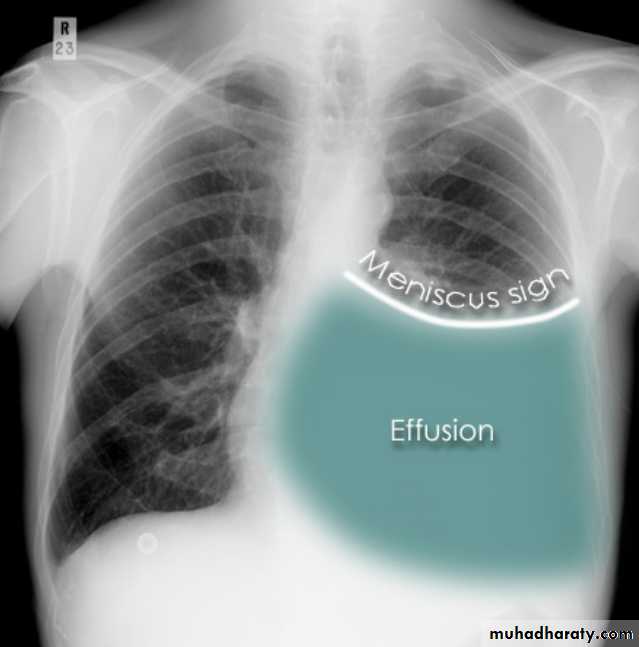

Plain radiographChest radiographs are the most commonly used examination to assess for presence of a pleural effusion, however it should be noted that on a routine erect chest x-ray as much as 250-600 ml of fluid is required before it becomes evident 6. A lateral decubitus film is most sensitive, able to identify even a small amount of fluid. At the other extreme, supine films can mask large quantities of fluid.

Both PA and AP erect films are insensitive to small amounts of fluid. Features include:

blunting of the costophrenic angle

blunting of the cardiophrenic angle

fluid within the horizontal or oblique fissures

eventually a meniscus will be seen, on frontal films seen laterally and gently sloping medially (note:

with large volume effusions, mediastinal shift occurs away from the effusion (note: if coexistent collapse dominates then mediastinal shift may occur towards the effusion)